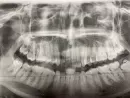

5 дней назад мне удаляли зуб мудрости. Сама десна заживает хорошо, но начал болеть зуб с этой же стороны, но верхний. 6 лет назад в нем удалили нерв, запломбировали канал. Периодически он меня продолжал беспокоить, но я повторно делала снимок и стоматолог ничего в нем не находил. Потом он не беспокоил и я забыла о нем. И вот после удаления зуба он почему то начал болеть, немного отдаёт в голову и нос, боль тянущая, чувствую при смыкании челюсти. На фото, он верхний 3 слева, а удаляли нижний левый крайний.

Да, описанные симптомы могут быть связаны с удалением 36 зуба. Но, всё же рекомендуем вам обратиться к стоматологу - терапевту для оценки состояния 26 зуба и качества лечения каналов.